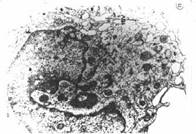

Fig. 8 Limfocit, ME. In

microscopia electronica se observa ca nucleul prezinta

cromatina densa si nu prezinta nucleol. Citoplasma este saraca in

organite